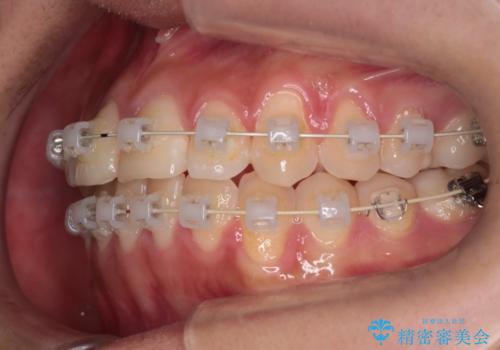

- 矯正装置

- 審美装置

- 治療期間

- 1年6ヶ月

装着時間に不安がある人は、ワイヤー矯正をおすすめしております。短期間で治療でき患者様にも満足していただきました。